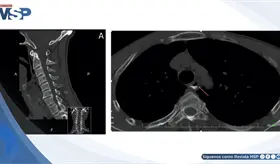

El paciente sufrió una ruptura hipofaríngea tras un accidente de tránsito inicialmente subestimado, requiriendo reevaluación, estudios avanzados y manejo multidisciplinario conservador.